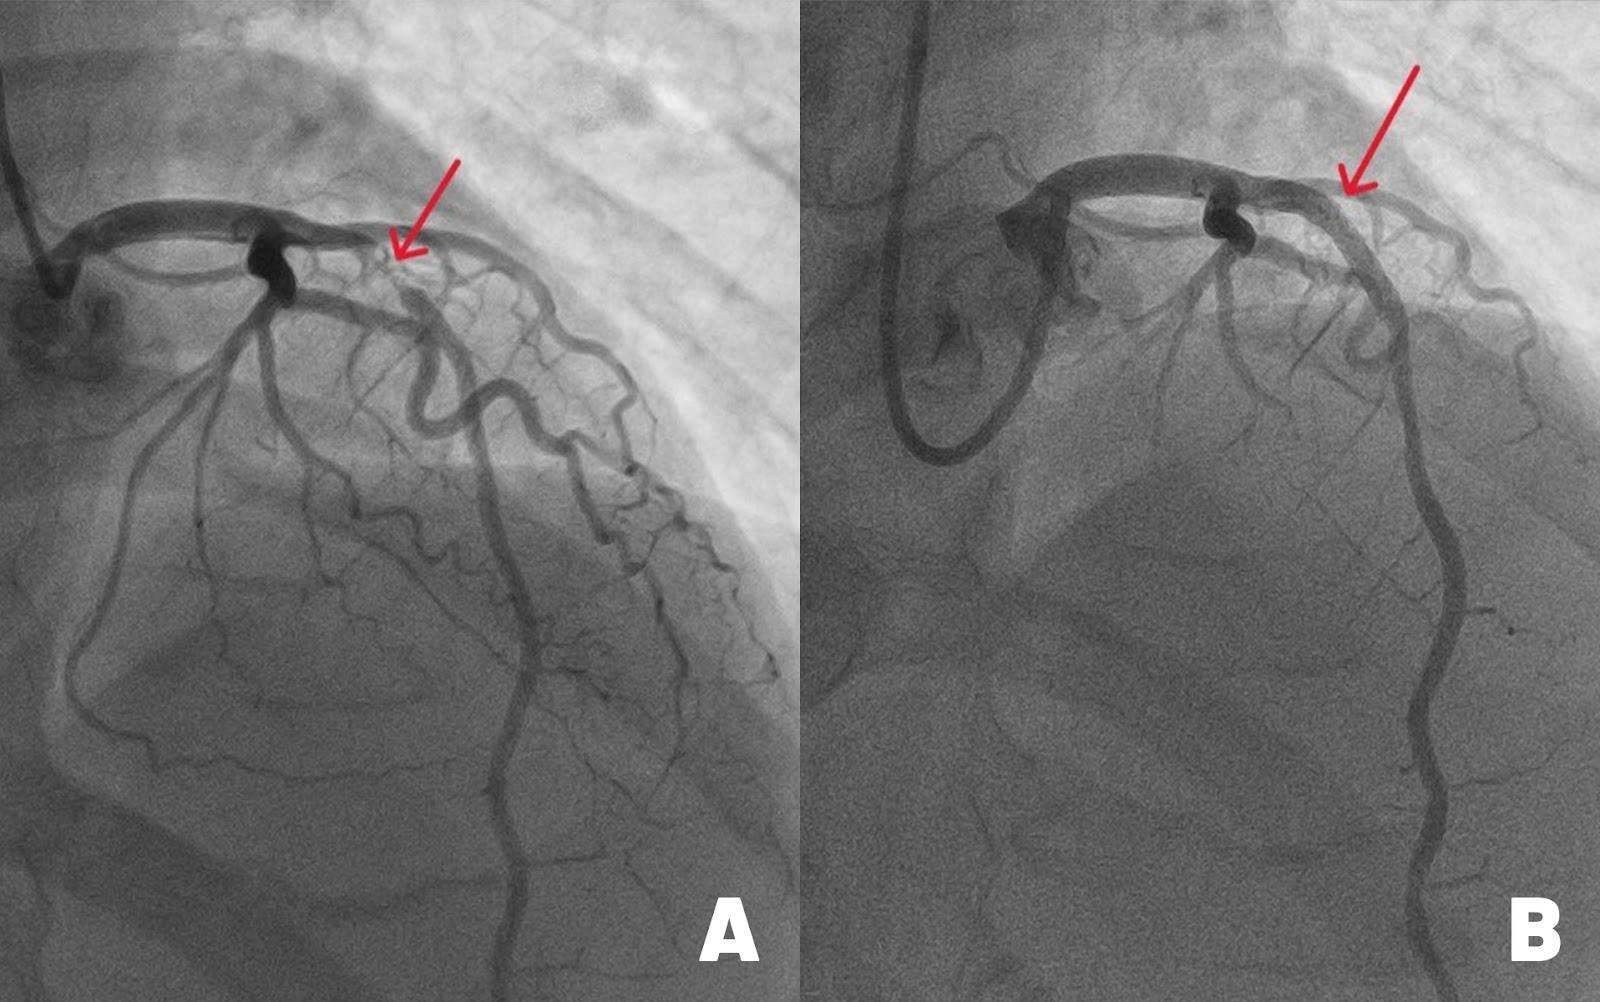

Các bác sĩ Trung tâm Can thiệp mạch BVĐK Tâm Anh TP HCM đặt stent nong mạch vành hẹp nặng dưới sự hỗ trợ của hệ thống chụp can thiệp mạch (DSA) cánh tay robot xoay 360 độ. Ảnh: BVCC